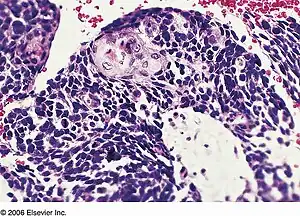

![]() | |

| Combined small cell lung carcinoma containing a component of squamous cell carcinoma | |